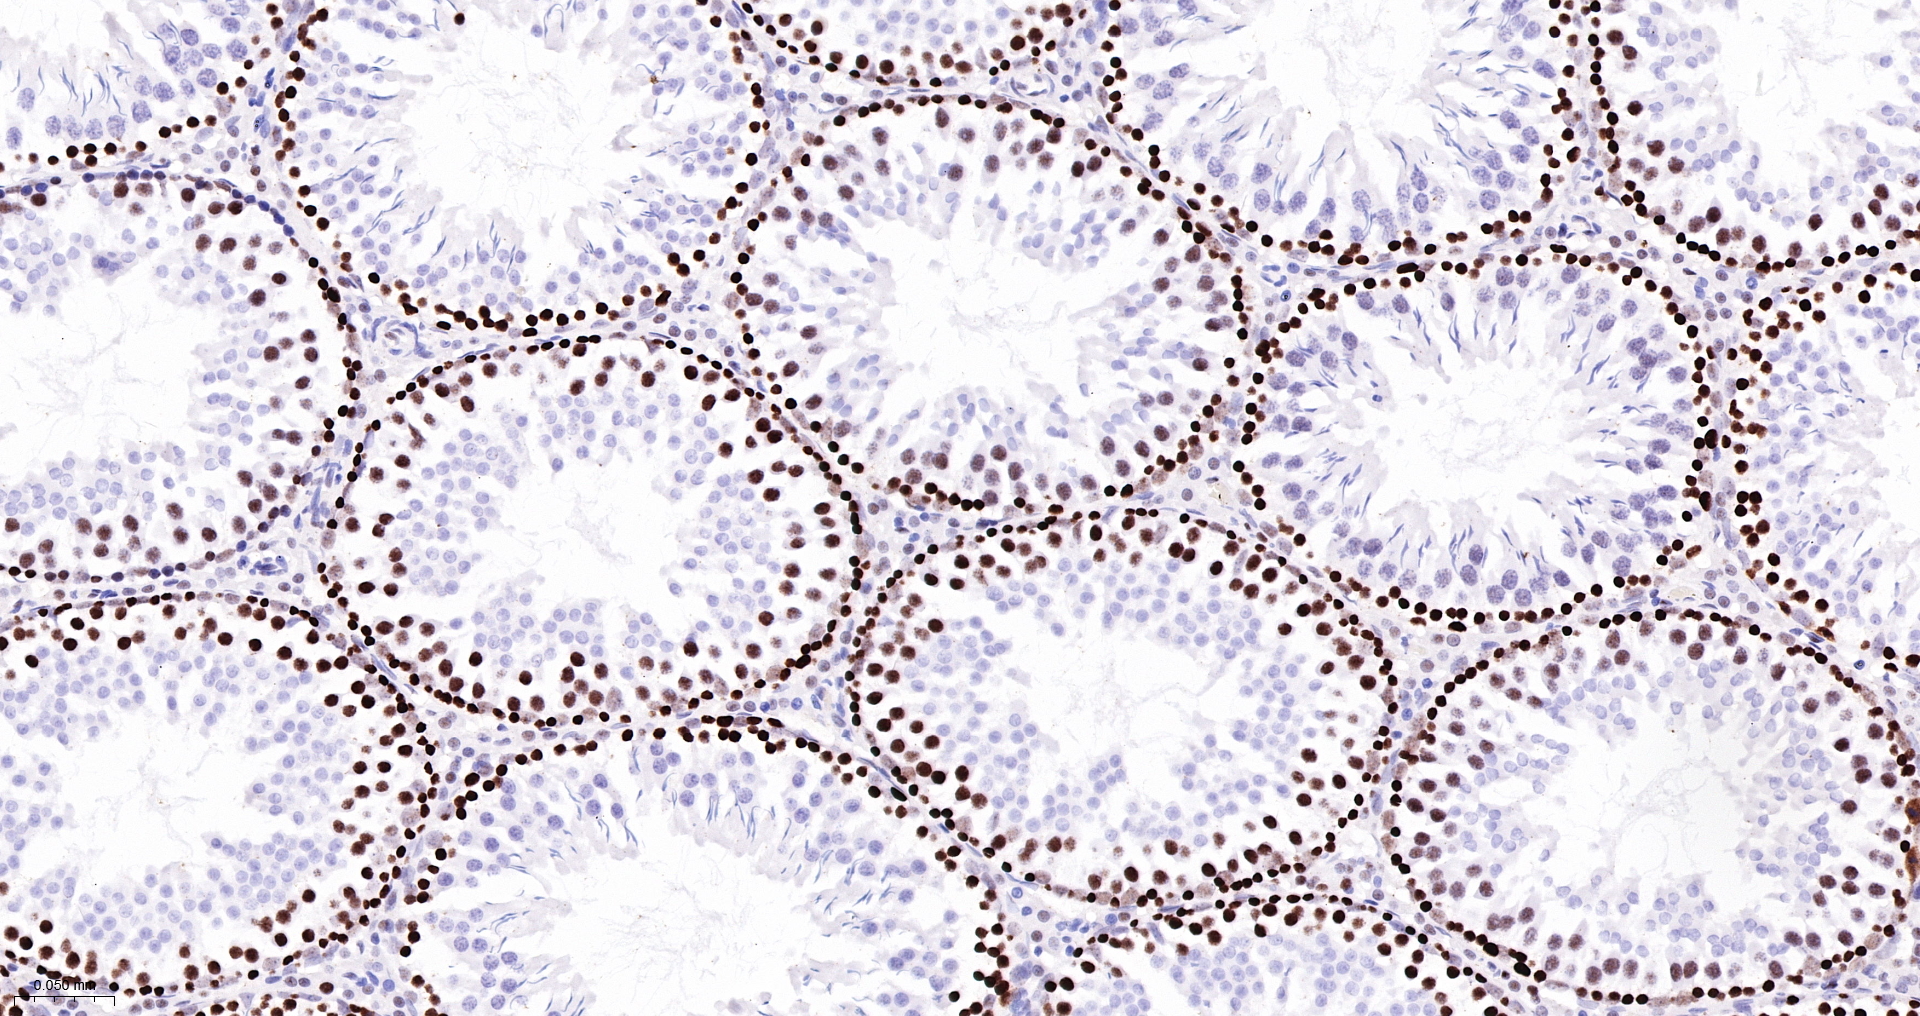

| MSH6 Recombinant Antibody |

| IHC-P |

IHC-P1:200-800 |